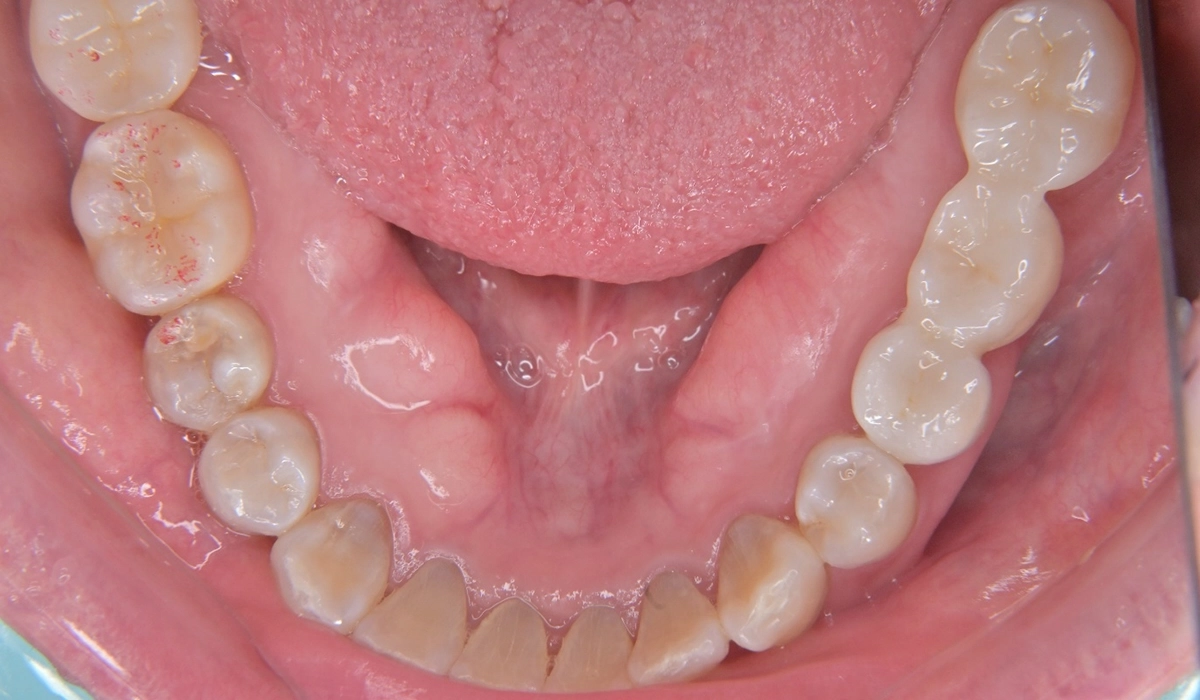

こちらが術前の口腔内写真になります。

問題点としては前歯部、臼歯部で進行したカリエスおよび前歯部歯肉増殖症、広範型慢性歯周炎StageⅡ GradeAが挙げられます。本症例では前歯部の審美性の回復について患者様との話し合いのうえセラミック修復による治療を選択しました。